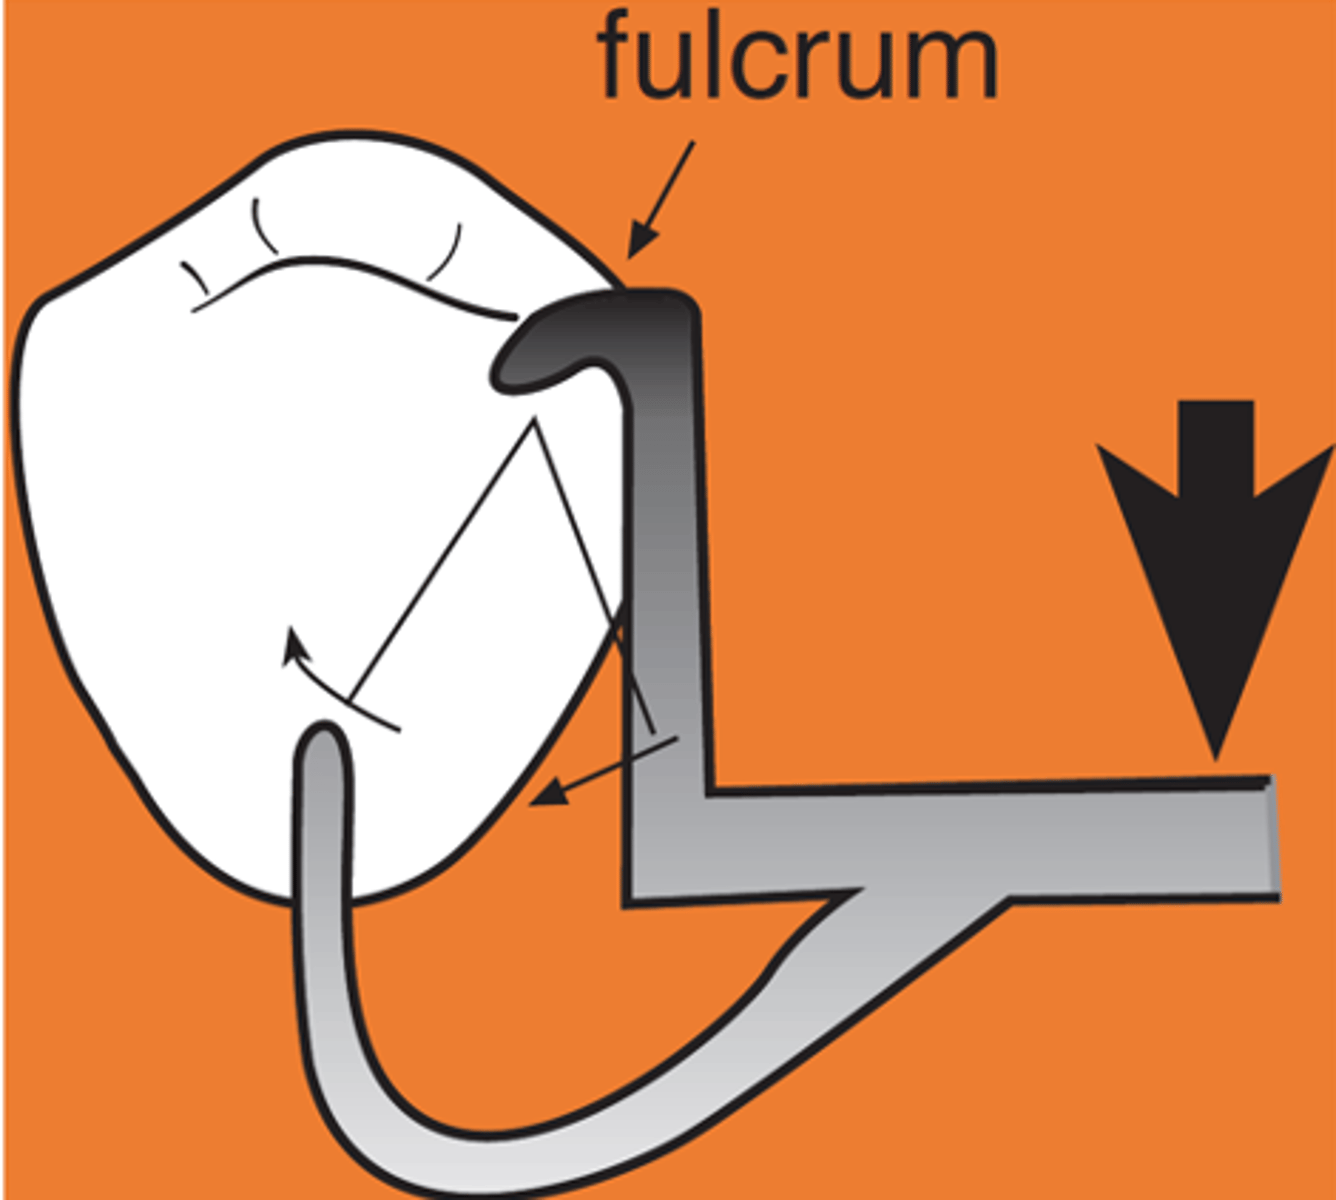

Indirect retainer

associated with extension base RPDs,

rotation occurs around rests: fulcrum line is through the most distal rest on each side, assist the direct retainers in preventing displacement through lever action on the opposite side of the fulcrum line when the denture base moves away from the tissues in rotation around the fulcrum line, prevents rotational displacement of denture from supporting soft tissues

An indirect retainer Ideally should be _______ from primary fulcrum line midway between the most distal rests, as far from fulcrum line as possible